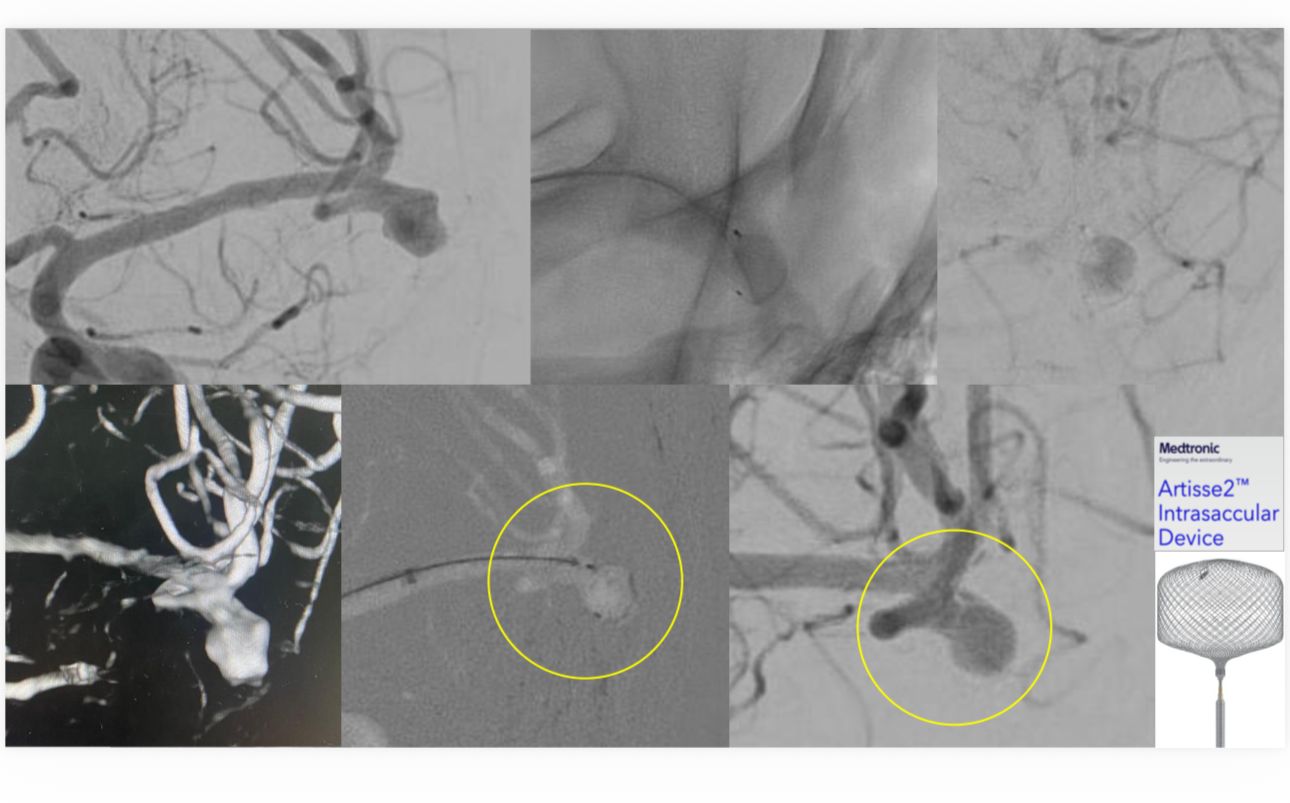

نجح فريق الأشعة العصبية التداخلية في  مستشفى الملك فهد الجامعي  التابع للمدينة الطبية الأكاديمية بجامعة الإمام عبدالرحمن بن فيصل، في علاج مريض يعاني من تمدد شرياني دماغي واسع العنق، وذلك في أول استخدام سريري لتقنية Artisse في المنطقة الشرقية.

وتمكّن الفريق الطبي من إغلاق التمدد الشرياني بالكامل باستخدام التقنية الحديثة، وخرج المريض من المستشفى وهو بكامل عافيته ، حيث تتميز  تقنية Artisse  بإمكانية زرع الجهاز داخل التمدد الشرياني بحيث يأخذ شكله بدقة، ما يسهم في تقليل زمن الإجراء وتقليل جرعة الأشعة والصبغة المستخدمة أثناء القسطرة، كما تتيح في كثير من الحالات تجنب استخدام مسيلات الدم بعد الإجراء، الأمر الذي يساعد في تسريع تعافي المريض وعودته إلى حياته اليومية بشكل أسرع.